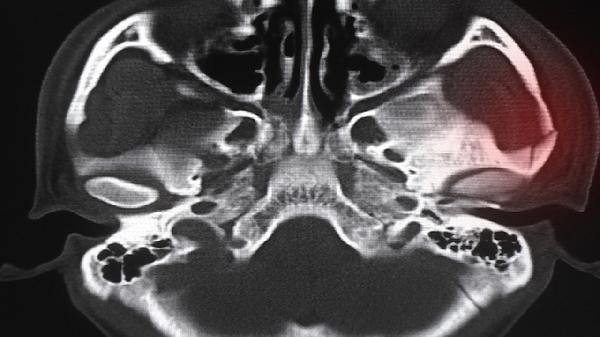

该综合征由体细胞GNAS基因嵌合突变引起,典型三联征包括多骨纤维结构不良、皮肤咖啡斑和性早熟。颅面骨受累可能导致视力障碍或听力下降,需多学科联合治疗。除双膦酸盐如帕米膦酸二钠注射液外,可能需神经外科干预视神经压迫,皮肤科处理色素沉着。